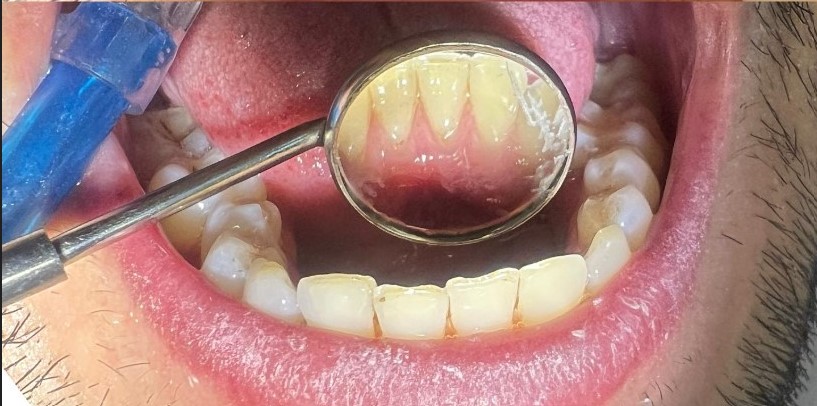

جرمگیری دندان یکی از خدمات مهم بهداشتی و درمانی در دندانپزشکی است که به حذف پلاکها، جرمهای سختشده (تارتار) و رنگدانههای سطحی روی دندانها و اطراف لثه کمک میکند. این جرمها معمولاً با مسواک و نخ دندان پاک نمیشوند و با گذشت زمان باعث التهاب لثه، خونریزی و بوی بد دهان میشوند.

در کنار جرمگیری، معمولاً از بروساژ (Polishing) نیز استفاده میشود تا سطح دندان صاف و براق شده و رسوبگیری در آینده کاهش یابد.